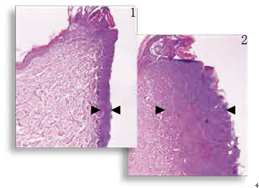

图1,2

减轻热损伤 组织学显示,对比标准的电切尖端切口(图2 ),表观切口(图1)明显热损伤减少